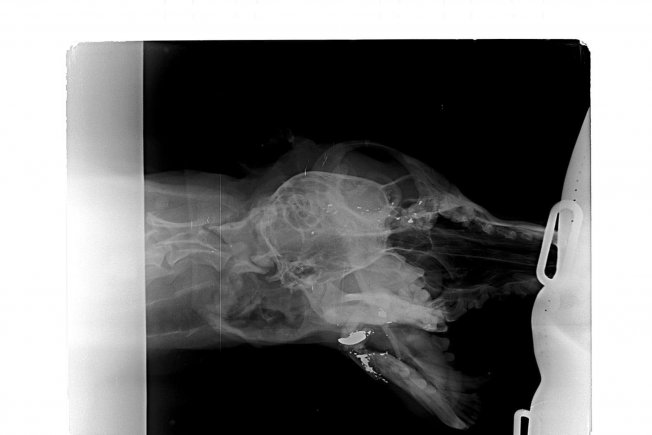

Pas imena Vini pronađen je u Ivancu prostrijeljene čeljusti. Prema njihovim navodima metak mu je doslovno otkinuo donju čeljust. Preživio je i sedam dana lutao u teškim bolovima zbog kojih nije mogao jesti ni piti, piše Varaždinski.

Tada je došao na prag ljudima koji su odmah kontaktirali 'Spas'. Veterinar Miljenko Cmrečak primio je psa kasno navečer, a čim se stabilizira, slijedi mu operacija.

U objavi navode kako je pas u kritičnom stanju, ali postoji nada da će izdržati tešku operaciju.